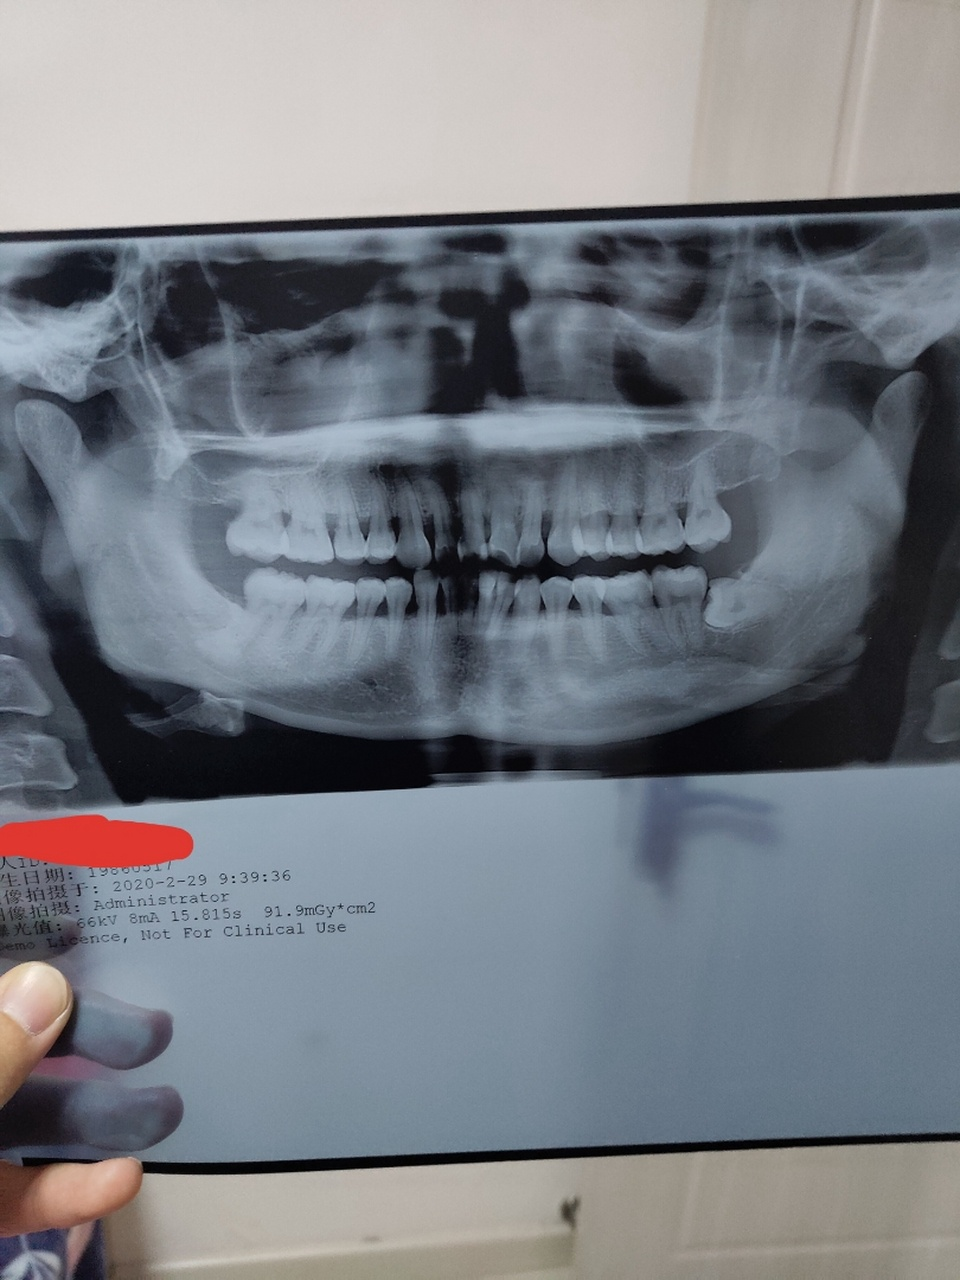

牙周炎与糖尿病互为危险因素,相互加重,糖尿病患者更易患重度牙周炎,牙周炎也增加血糖控制难度。

1.高糖环境:糖尿病高血糖利于细菌繁殖,加重牙周炎症。

2.免疫低下:糖尿病患者免疫功能弱,抗感染能力差,炎症更难控制。

3.炎症因子:牙周炎释放的炎症因子干扰胰岛素作用,升高血糖。

4.恶性循环:牙周炎未控制,血糖难降;血糖失控,牙周炎恶化。

5.协同治疗:控制牙周炎有助于降低糖化血红蛋白水平。

糖尿病患者必须重视牙周健康,定期口腔检查。牙周炎患者也应筛查糖尿病。两者需同步治疗,互相促进。严格控制血糖是牙周治疗的前提。多学科协作效果更佳。